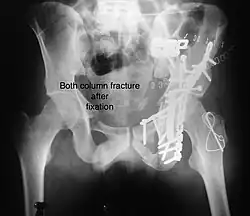

Both column fracture after fixation with screws and plates -

Function after fixation both column fracture